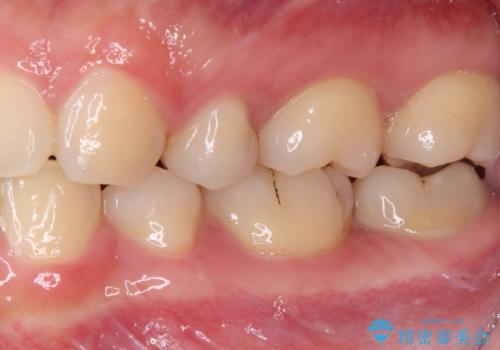

奥歯に物が挟まる セラミックインレーでのむし歯治療

- 食事の度に物が挟まるとのことで来院された患者様です。

目視でも欠損が認められ、レントゲン写真からもむし歯が認められる状態でした。

患者様と相談の上、セラミックインレーで精密な修復治療を行うこととしました。